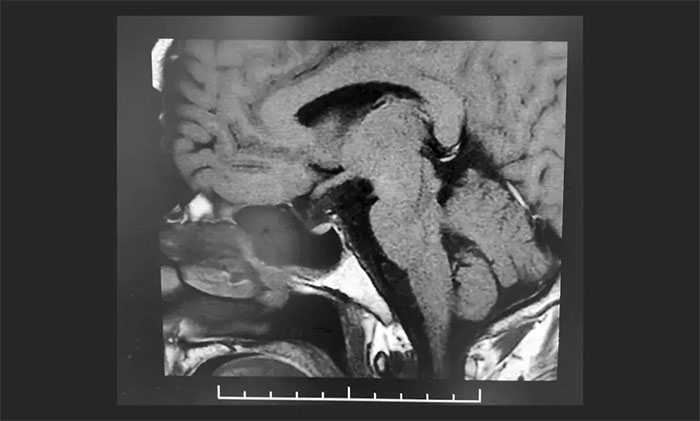

▲ 术后影像显示肿瘤被切除